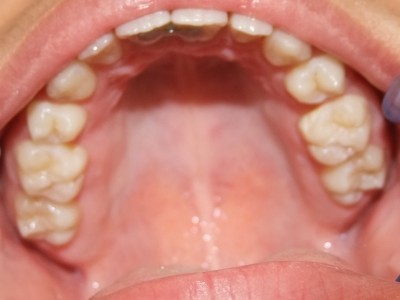

Na behandeling

Retentie fase: Wrap en C-CBar

14-47 maanden: Volledig banden/slotjes in de boven-en onderkaak

(omdat er hier blijvende kiezen ontbraken moesten er kiezen getrokken worden en de ontstane ruimtes gesloten, dit verklaart de langere behandeltijd)